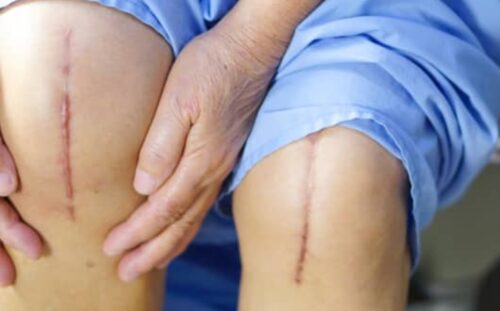

1977 yılında Uşak’ta doğdu ve babasının görevinden dolayı Türkiye’nin değişik şehirlerinde büyüdü. Tıp derecesini İzmir Dokuz Eylül üniversitesi Eğitim ve Araştırma hastanesinden 2001 yılında aldı. Aynı hastanede Ortopedi ve Travmatoloji uzmanlık eğitimini tamamlayarak Ocak 2008’de Ortopedi ve Travmatoloji Uzmanı oldu.